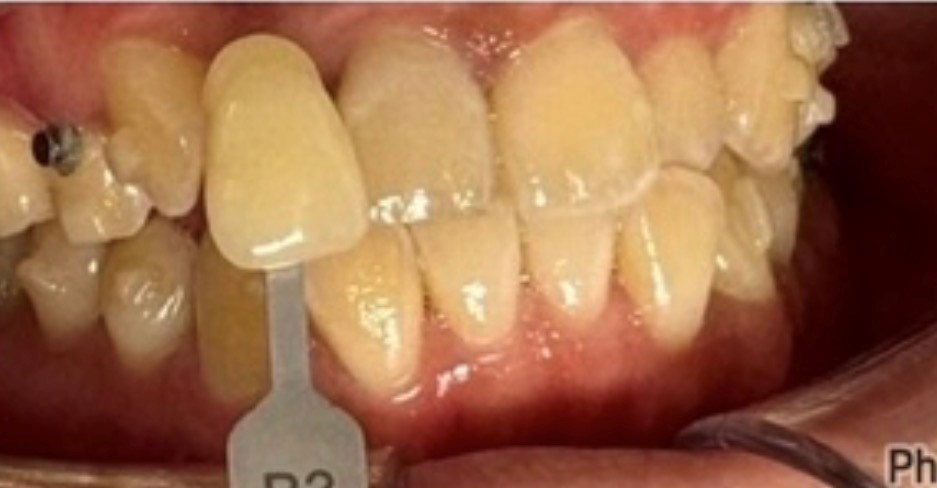

症例画像

治療期間 1回(7分×10分×10分)

治療費用 9800

主訴 歯の着色

治療内容 オフィスホワイトニング

副作用リスク→知覚過敏のようなしみ、痛み。アタッチメントの下の色むら